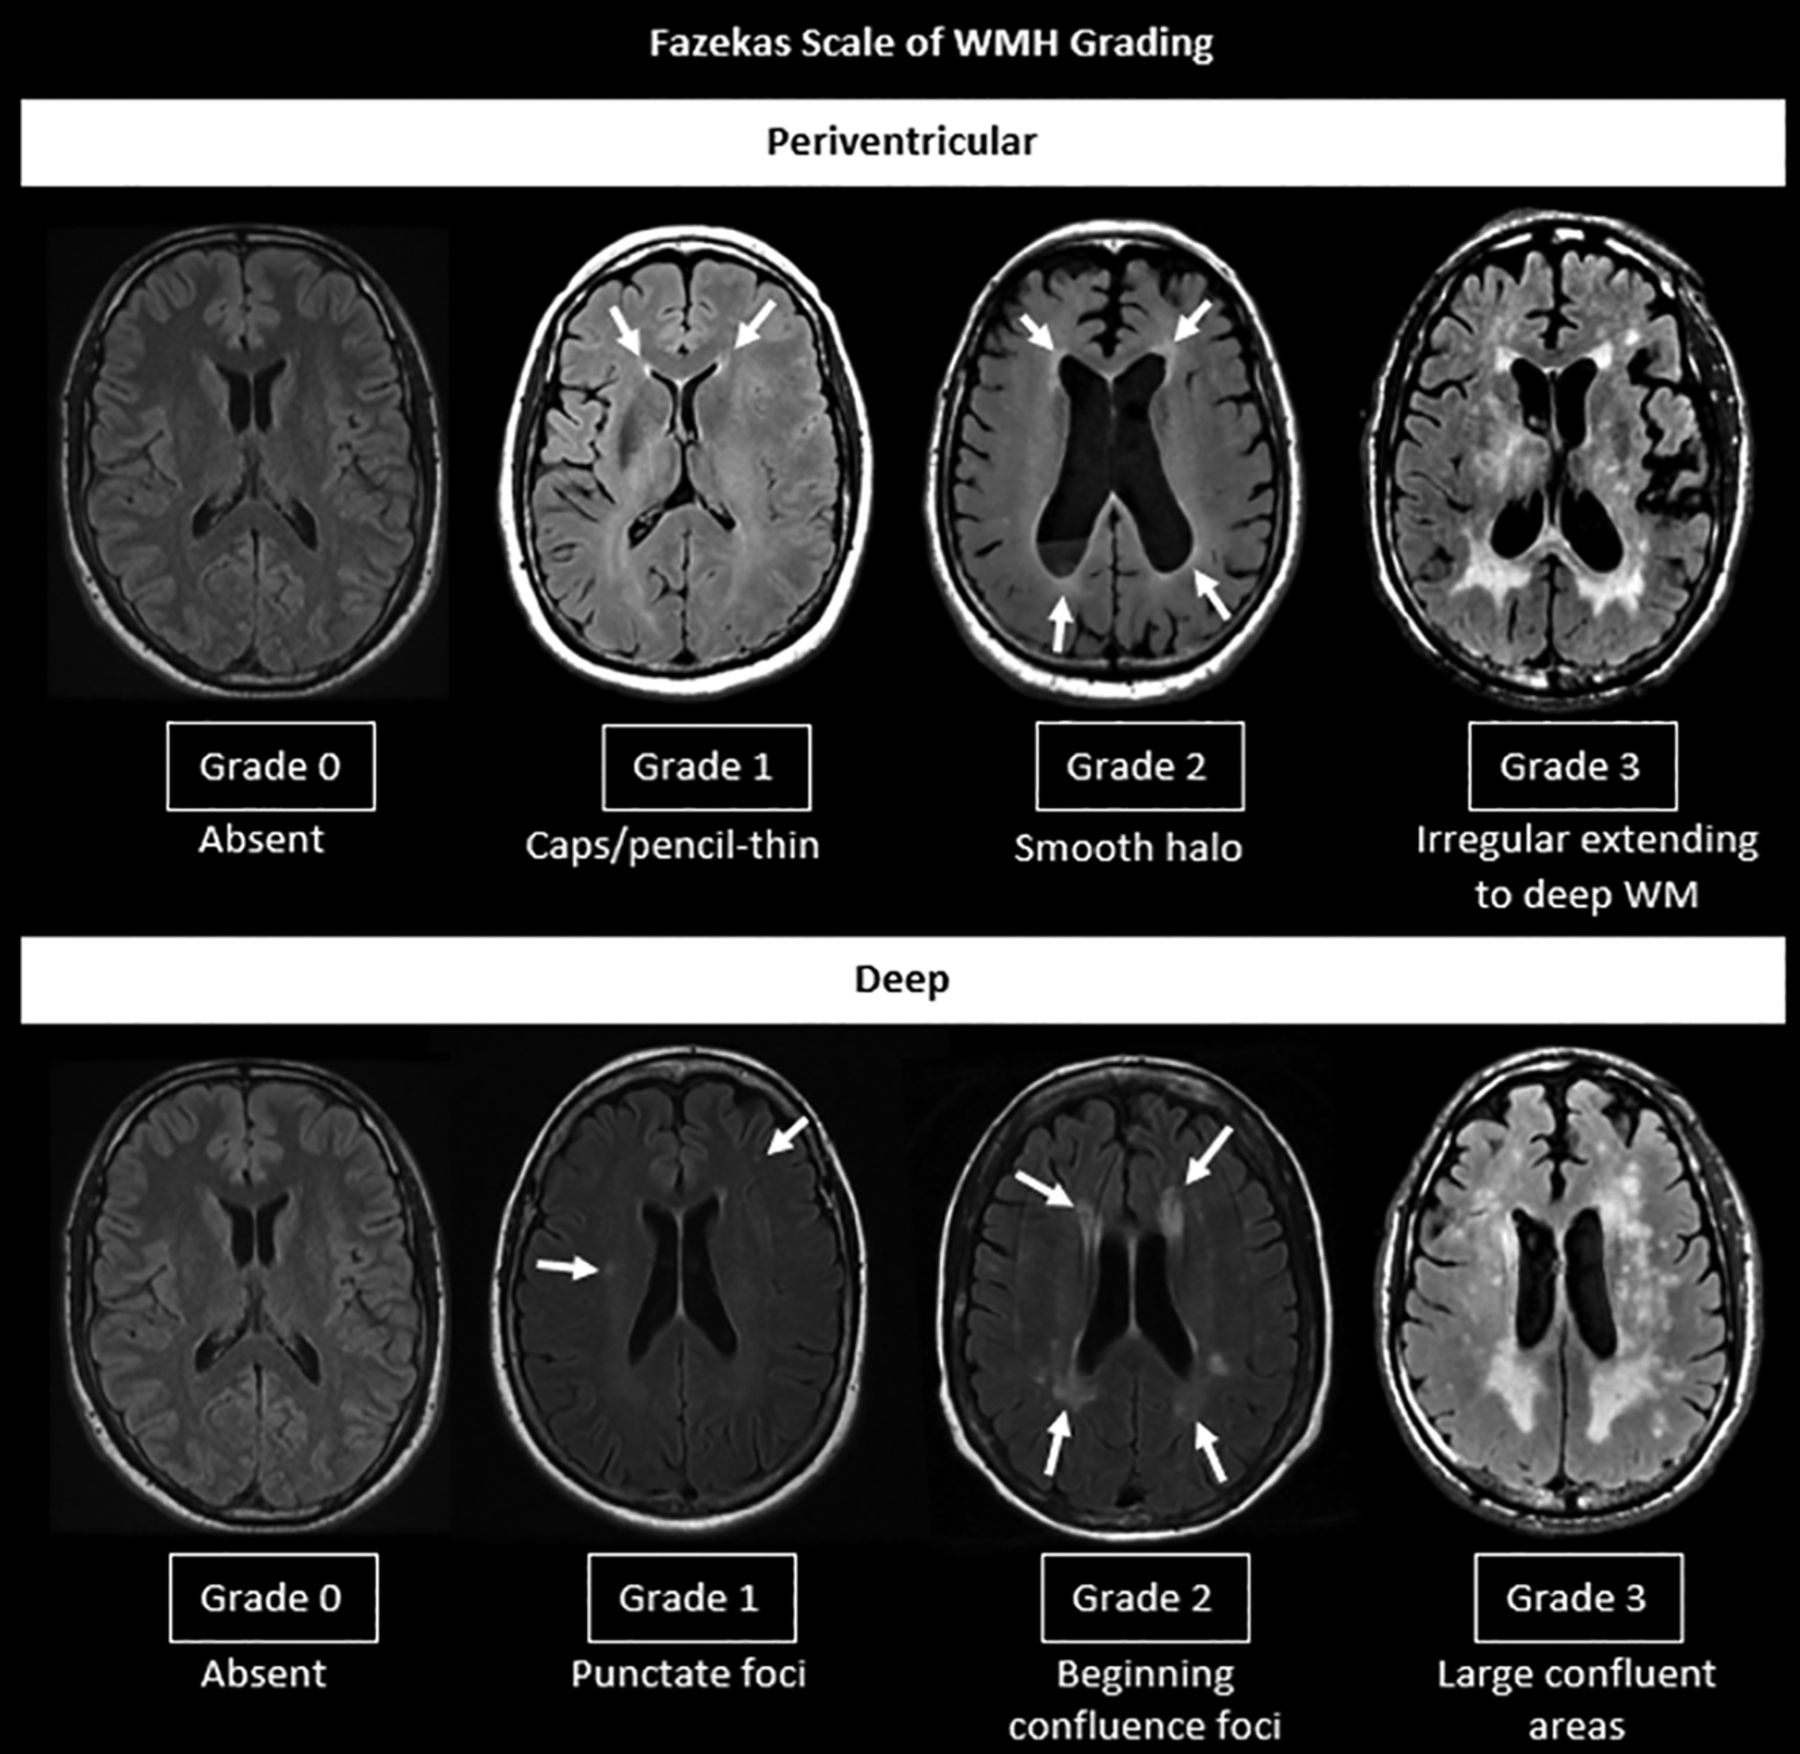

Fazekas scale of WMH grading.

WMH of presumed vascular origin are characterized by hyperintense lesions on T2 FLAIR and decreased attenuation on CT in the periventricular/deep cerebral white matter, subcortical gray matter, basal ganglia, and brainstem. Although the Fazekas visual rating scale (Fig 3) is the most commonly used method to assess the burden of WMH, there is a lack of a rigorous method to accurately quantify the WMH burden.34 Furthermore, a fronto-occipital gradient was used in few studies to describe the difference in the severity of WMH between the frontal and occipital lobes.33,35 It was suggested that patients with obvious occipital-dominant WMH were more likely to develop complications from SVD such as lobar intracranial hemorrhage than healthy controls.35 The severity of WMH is strongly associated with cerebrovascular disease, vascular risk factors, gait disturbance, cognitive symptoms, and poststroke functional outcomes.3,11